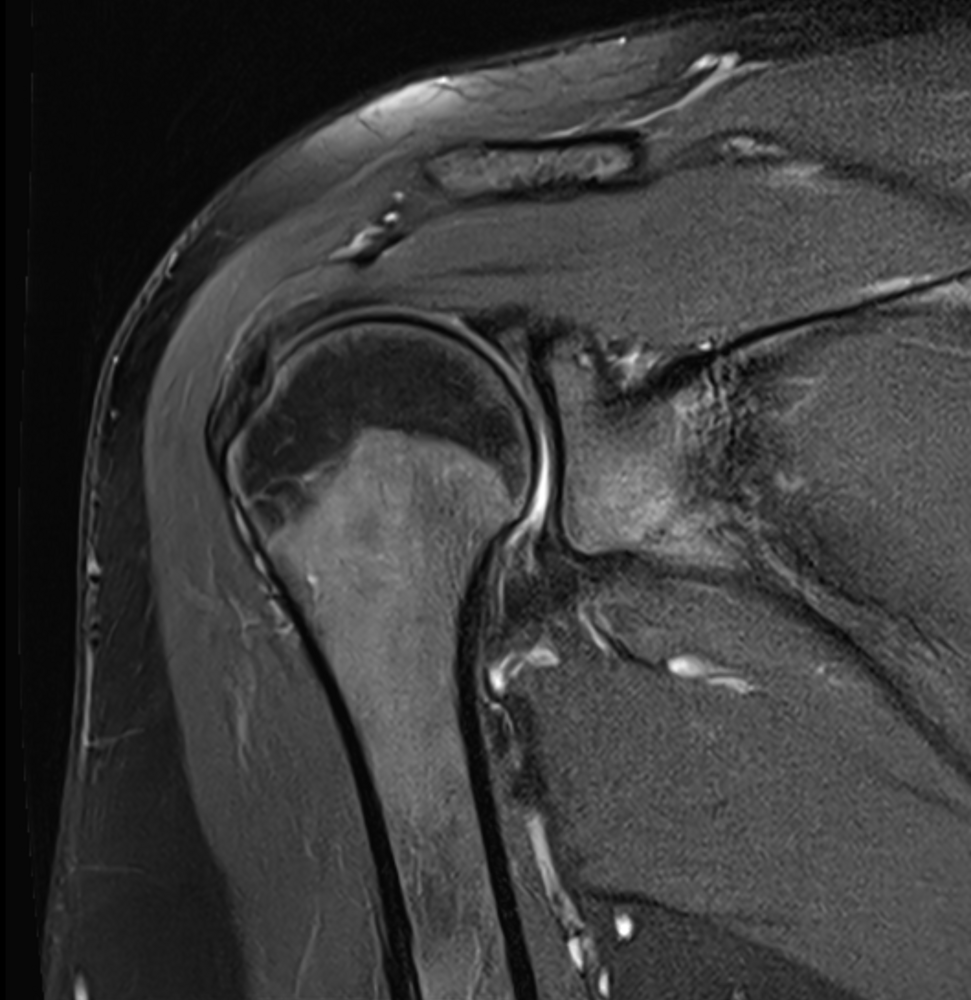

MRT der Gelenke

Die MRT spielt eine entscheidende Rolle bei der Diagnose und Beurteilung degenerativer Gelenkerkrankungen, wie z.B. Arthrose. Durch hochauflösende Bilder ermöglicht sie die Visualisierung von Veränderungen im Gelenkknorpel, den umgebenden Weichteilen (z.B. Menisci und Bänder) und der Knochenstruktur. Dies ermöglicht eine präzise Beurteilung des Krankheitsfortschritts und hilft bei der Planung gelenkerhaltender oder endoprothetischer Behandlungsstrategien.

Bei Unfällen bietet die MRT eine detaillierte Darstellung von Weichteilverletzungen wie Bänder- oder Sehnenrisse sowie von Knochenbrüchen. Sie ermöglicht eine genaue Lokalisierung und Beurteilung des Ausmaßes der Verletzungen, was für die Entscheidung über die optimale Behandlung wichtig ist.

Durch die Nicht-Invasivität und die Möglichkeit, verschiedene Gewebestrukturen genau zu unterscheiden, ist die MRT ein unverzichtbares Instrument in der orthopädischen Diagnostik. Sie ermöglicht eine frühzeitige und präzise Diagnosestellung, was zu einer effektiveren Behandlung und einer verbesserten Patientenversorgung führt.